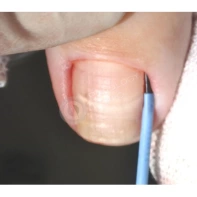

- Хирургическое иссечение. Под местной анестезией при помощи скальпеля удаляется вросший край ногтевой пластины вместе с зоной роста, затем на рану накладываются швы. В некоторых ситуациях вместе с резекцией ногтя проводится пластика околоногтевого валика, позволяющая повысить эффективность оперативного вмешательства и добиться стойкой ремиссии заболевания.

- Радиоволновое удаление вросшего ногтя. При воздействии радиоволн высокой частоты происходит испарение клеток и коагуляция тканей при низкой температуре (38–80°С). Это называется «холодным» разрезом тканей, такая процедура длится не дольше получаса, сопровождается минимальной болезненностью и отеком. Заживление происходит без образования грубого послеоперационного рубца.

- Лазерная резекция. Лазером удаляется вросший кусочек ногтя и поврежденные слои ногтевого валика. Затем прижигается разросшийся участок ростковой зоны. При этом лазерные пучки одновременно стерилизуют ногтевое ложе, исключая риск развития инфекционных процессов и ускоряя процесс заживления. Операция занимает 15–20 минут, имеет минимальную травматичность. Период восстановления после такого вмешательства относительно короткий.

- Непосредственное удаление патологически измененных тканей.

- Обработка раны и наложение стерильной повязки.

Лечение вросшего ногтя СО2-лазером

Пациентам с обострением вросшего ногтя, который беспокоит длительное время, может быть показано выполнение краевой резекции СО2-лазером. Облегчение и снижение болевого синдрома наступает непосредственно после вмешательства. Подробнее об операции рассказывает хирург-онколог Георгий Исаевич Исмаилов.